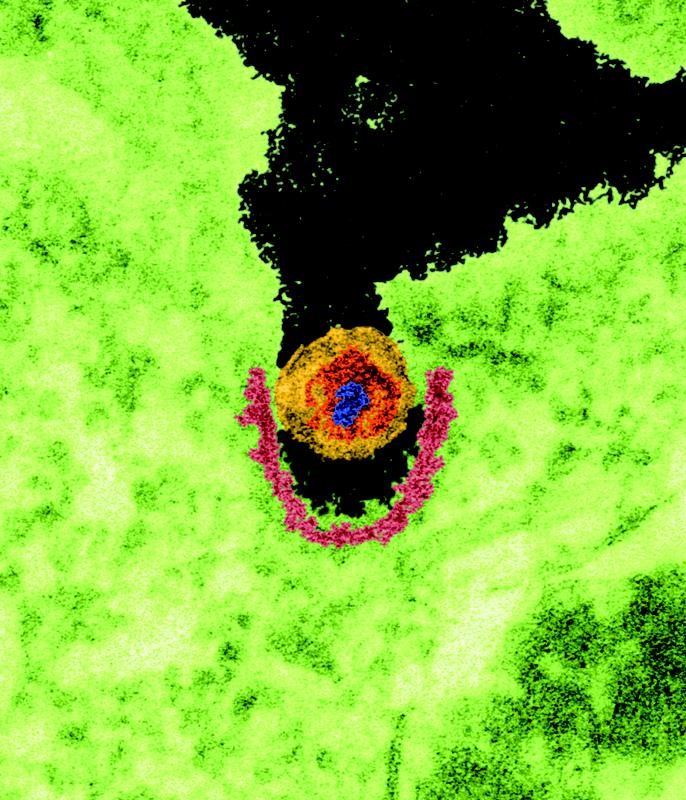

Porcine endogenous retroviruses